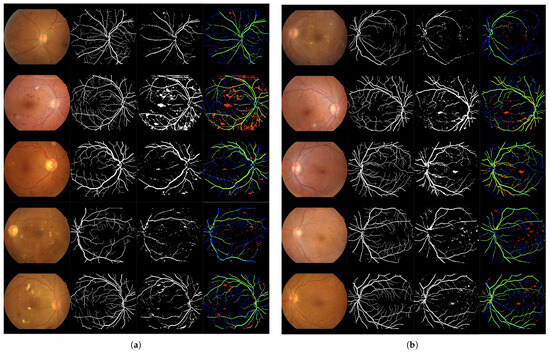

Figure 7.

Set of 4-image sequences illustrating the test results of Experiment 3 graphically. The first image is the original input, the second shows the ground truth vessel locations labeled by experts, the third corresponds to the output of the ANN from experiment 3, and the fourth visualizes the outcome in terms of true positives (green), false positives (red), false negatives (blue), and true negatives (black). Panel (a) displays the first five test images, while panel (b) shows the last five.